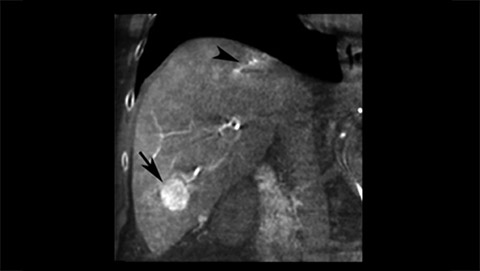

XperCT extends the capabilities of the interventional suite offering CT like imaging to visualize bone, soft tissue and vessels. This CT-like image can be acquired with or without contrast agent right in the angio suite and overlaid with the 3D vascular image. It helps identify subtle soft-tissue lesions and supports in room characterization in arterial and post-arterial phase.

XperCT extends the capabilities of the interventional suite offering CT like imaging to visualize bone, soft tissue and vessels in case of contrast enhanced acquisition. XperCT supports fast abdominal protocols with 5 to 8 seconds acquisition time for excellent image quality while significantly minimizing respiratory artifacts. The XperCT 3D volume is displayed automatically within 8 to 15 seconds after the acquisition and confirms selective targeting of hepatic lesion and helps avoid untargeted embolization and drug delivery.